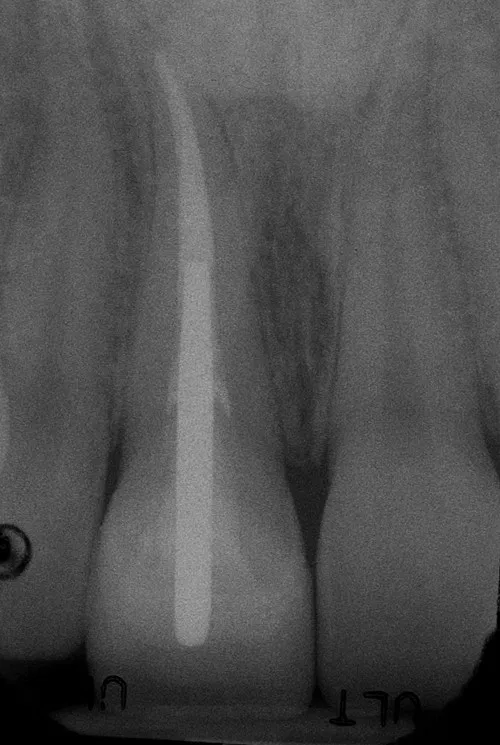

Ceramic Post/Core; Ceramic Crown-Bonded

Before:Â Tooth #8 (upper right central incisor) has a history of trauma and root canal therapy. Re-treatment of the root canal filling was required.

After: Followed by delivery of a custom ceramic post/core foundation, and a bonded all-ceramic full coverage single restoration (crown).